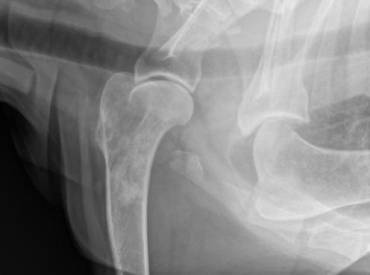

Osteosarcoma apendicular canino

El osteosarcoma (OSA) apendicular es el tumor...